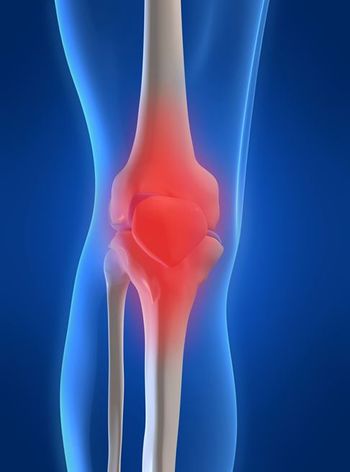

Synovitis predates and is associated with the development of radiographic osteoarthritis, new findings suggest. Treating synovitis in knee OA may help reduce disease progression and relieve symptoms. Details here.